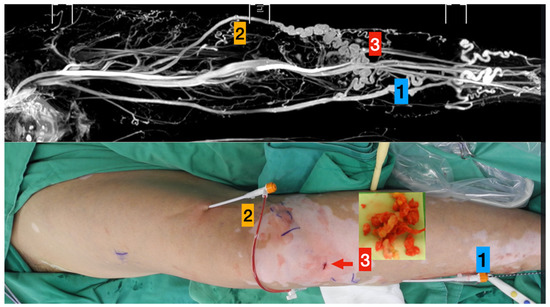

- Left great saphenous vein

- Accessory saphenous vein

- Major communicating tributaries.

- Primary truncal ablation of the great saphenous vein.

- Additional ablation of the accessory saphenous vein.

- Phlebectomy though the small incisions (red arrow).